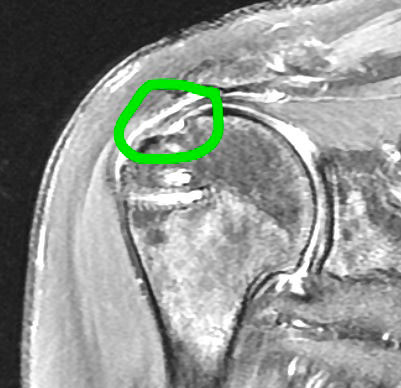

Supraspinatus Tendon Tear

Tear is on the left and the healed repair is on the right